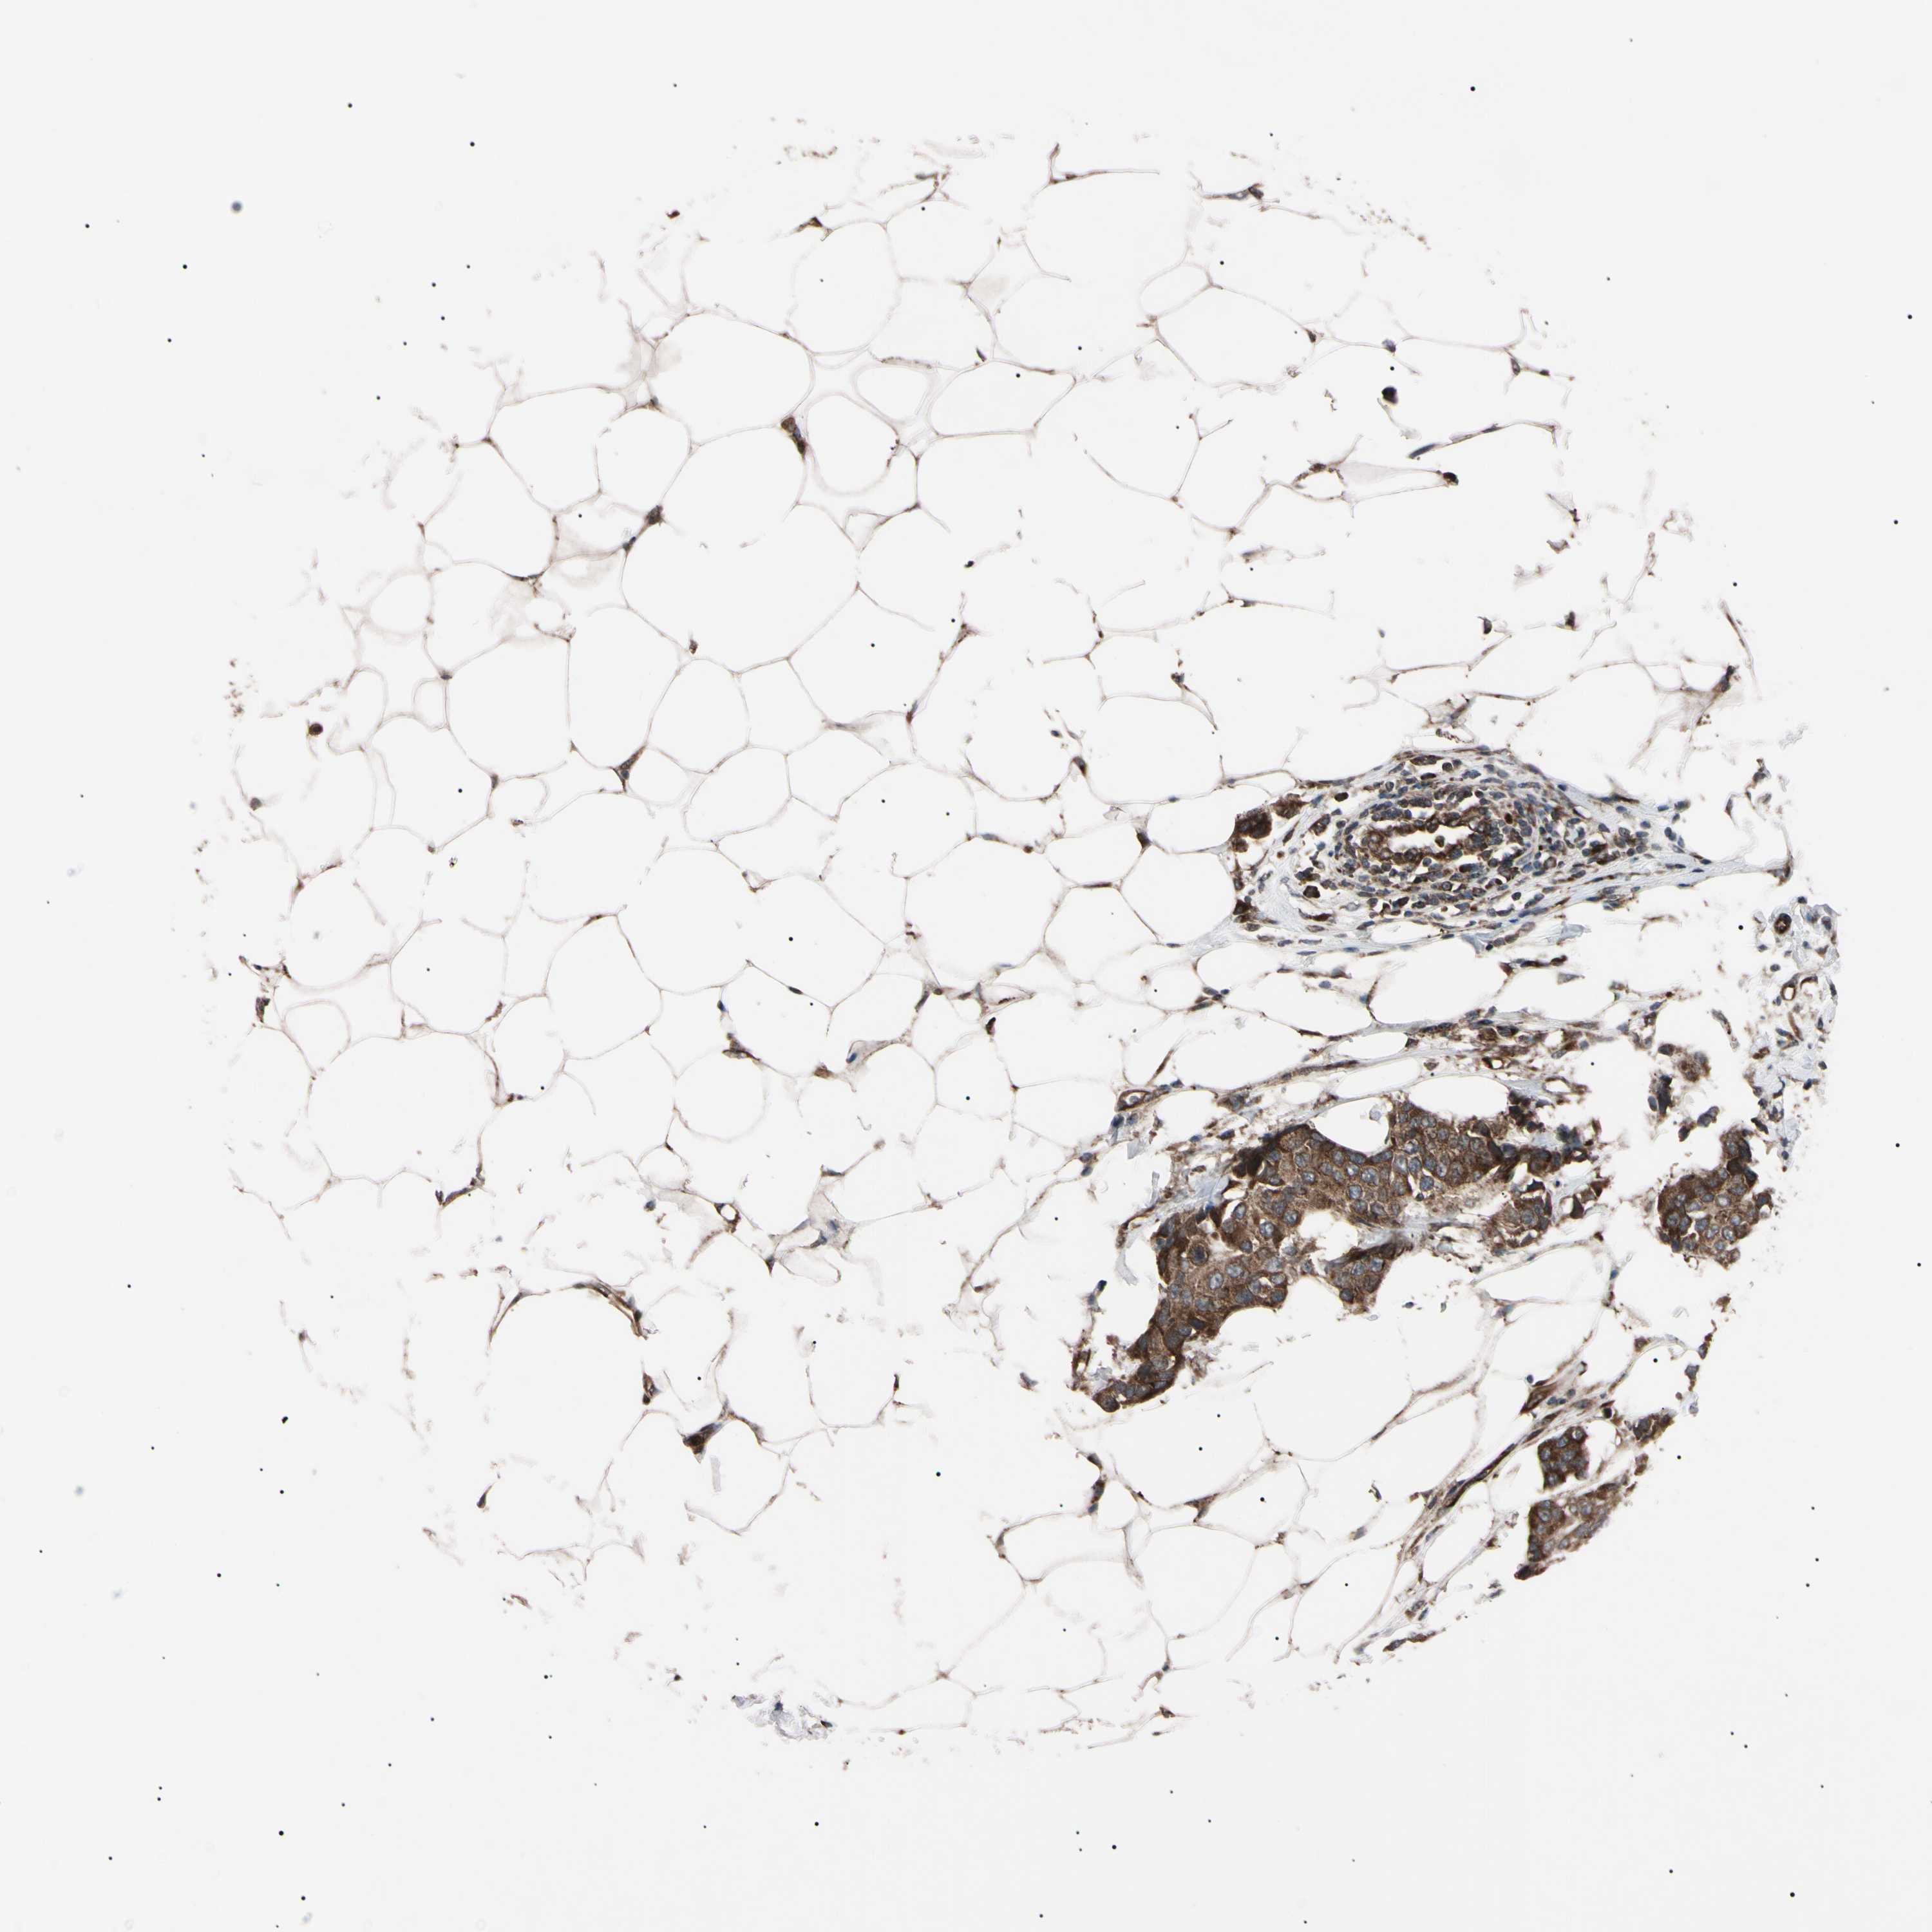

BRCA TCGA BRCA VALIDATION PROTEIN EXPRESSION